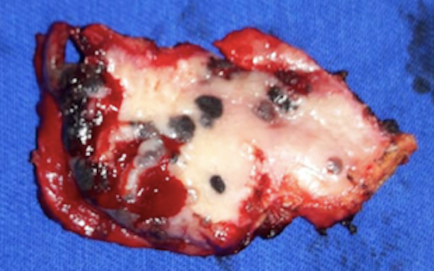

A oroscopia revelou placa enegrecida no palato duro direito, medindo cerca de 1cm, com área ulcerada, acompanhada por lesões-satélites, e placa enegrecida na gengiva superior direita, com aproximadamente 2,5cm (Figuras 1 e 2). O exame clínico não apresentou outras lesões suspeitas nem linfonodos cervicais palpáveis. A tomografia computadorizada de crânio, pescoço, tórax, ultrassonografia de abdome e exames laboratoriais não mostraram achados significativos. Procedeu-se à biópsia incisional que apresentou neoplasia de crescimento infiltrativo, constituída por células anaplásicas, contendo grande quantidade de melanina nos citoplasmas, com intenso grau de pleomorfismo e atipias nucleares (Figura 3). O perfil imuno-histoquímico foi compatível com melanoma melanótico maligno infiltrativo com coloração positiva de HMB-45 e melan A (Figura 4).

O paciente foi submetido à ressecção de palato duro, fragmento de gengiva superior medial, dentes e processo alveolar superior à direita, seguida de reconstrução de palato, utilizando-se retalho de mucosa jugal direita (Figuras 5 e 6). O exame histopatológico da peça cirúrgica confirmou o diagnóstico prévio de melanoma maligno invasivo, com componente in situ presente e extenso na periferia da lesão, ulceração presente, invasão perineural e angiolinfática ausentes e margens cirúrgicas livres de neoplasia. Optou-se por não realizar ressecção de linfonodos cervicais e tratamento adjuvante. O paciente não apresentou sinais de recidiva nem disfunções associadas ao procedimento cirúrgico durante seguimento de 12 meses (Figura 7).